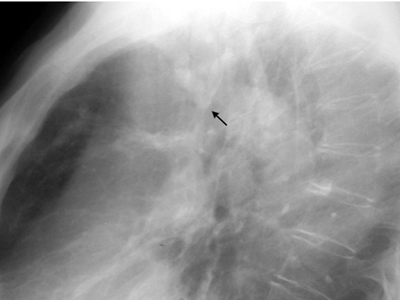

Bronchial Cast

"Gloved finger" appearance. Branching density.